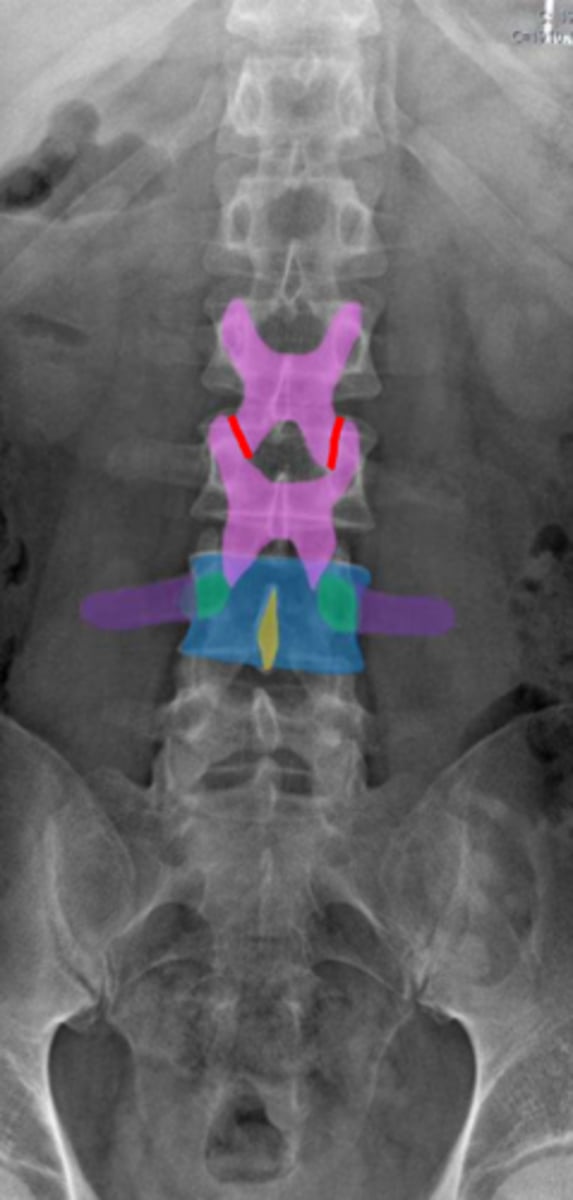

lumbar

What vertebrae is being examined?

lumbar vertebral body

Identify the blue structure

pedicles

Identify the green structure

transverse processes

Identify the purple structure

spinous processes

Identify the yellow structure

joint space between superior and inferior articulating facets

Identify the red line

intervertebral foramen

Identify the orange structure

pedicles

Identify the green structure